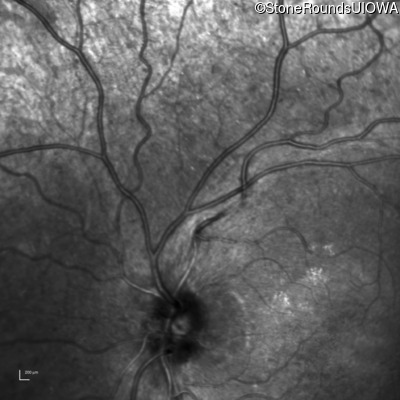

Infrared Fundus Photograph - Left - 20/20 -1

Exemplar